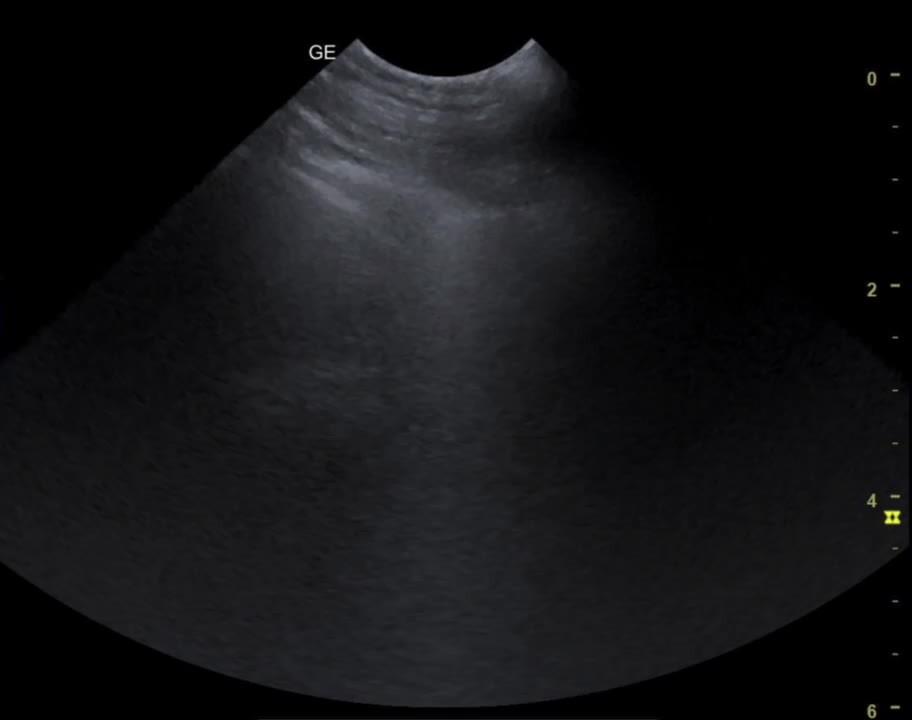

B-lines, lung ultrasonogram

B-lines are bright (hyperechogenic) vertical artifacts that extend from the pleural interface through the screen. They indicate fluid accumulation within the interstitial space.

Courtesy of Dr. Andrew Linklater.